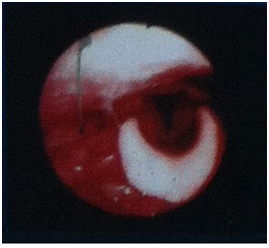

The tumor is histopathologically characterized by intense proliferation of myoblastic spindle cells wiyh chronic lymphocytic infiltration of the stratum.1,2 Three histological types are reported: a) mucosal, vascular and inflammatory areas resembling computed nodular peritonitis (Nodular fasciitis – like type), b) spindle cells intercalated with inflammatory cells (Lymphocytes, Eosinophils and Plasmacytes) resembling fibrous tissue (Fibrous histiocytoma - like type) and c) dense, squamous collagen, looks like fibrous scar tissue (Desmoid or scar tissue type) (Figure 3 & 4).

Figure 3 Histopathology specimen (HE, X100) with squamous cells, mucoid and inflammatory infiltration and spindle cells.

The diagnosis is based on histological examinations and is documented by immunodiagnosis and immunohistochemistry.1,2,3,16 In our case, the cells were positive for SMA, Caldesmon and Calponin while exhibiting inflammatory infiltration, myxoid degeneration and scattered spindle cells as in the second histological type above described.